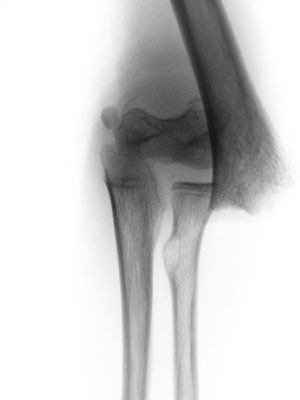

8-jähriger Junge mit ellenbogennahem Oberarmbruch. Der Bruch musste operativ eingerichtet werden. Stabilisierung mit Drähten, Gips für 3 Wochen. Die Drähte werden nach 3 Monaten wieder entfernt.